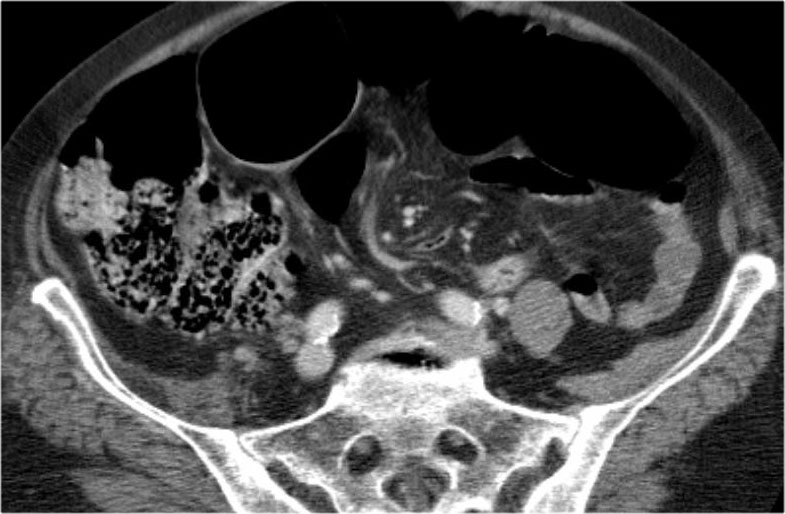

Tắc ruột dạng quai kín với các quai ruột giãn xếp theo hình nan hoa. Có dày thành ruột và phù nề mạc treo gợi ý thiếu máu cục bộ

Một hình ảnh quan trọng khác của tắc ruột dạng quai kín là các quai ruột non giãn xếp theo hình nan hoa với các mạch máu mạc treo hội tụ về một điểm trung tâm.

Hình ảnh này hầu như luôn do xoắn ruột non gây ra.

Các dấu hiệu thiếu máu cục bộ trong tắc ruột dạng quai kín tương tự như ở bệnh nhân thiếu máu mạc treo do các nguyên nhân khác:

- dày thành ruột

- phù nề mạc treo

- cổ trướng

- sự ngấm thuốc của thành ruột trong thiếu máu cục bộ có thể bình thường, tăng hoặc giảm.

Nếu quai kín dài hơn và định hướng vuông góc với mặt phẳng cắt, chúng ta sẽ thấy một cụm quai ruột như trong ca lâm sàng bên trái.

Đôi khi điều này khó nhận biết chỉ trên các lát cắt ngang và các tái tạo mặt phẳng coronal hoặc sagittal có thể hữu ích.

Trong ca này, cũng có phù nề mạc treo và cổ